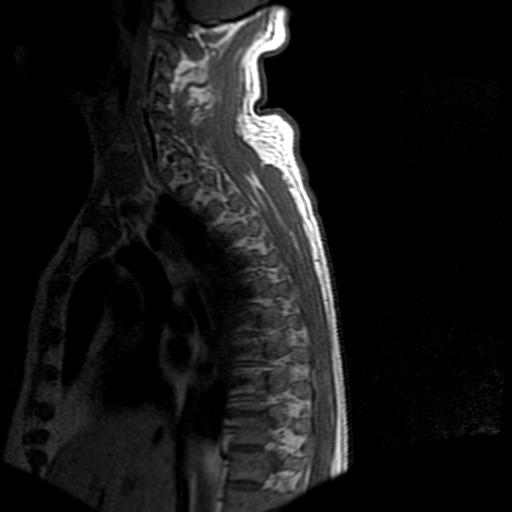

标题: MRI0985:胸椎.68岁男性,胸部疼痛,

68岁男性,胸部疼痛,不适。

t7椎体前1/3信号略减低,椎体上下面凹陷,相应脊髓几周边软组织信号未见改变。考虑:椎体退变。

胸7椎体楔状变形及信号异常,附件未见明显异常信号.椎间隙正常.未见软组织块影.考虑骨质疏松所致压缩性骨折可能大.

胸7椎体楔状变形及信号异常[t1t2 均为低信号],附件未见明显异常信号.椎间隙正常.未见软组织块影.考虑陈旧性压缩性骨折伴退变。